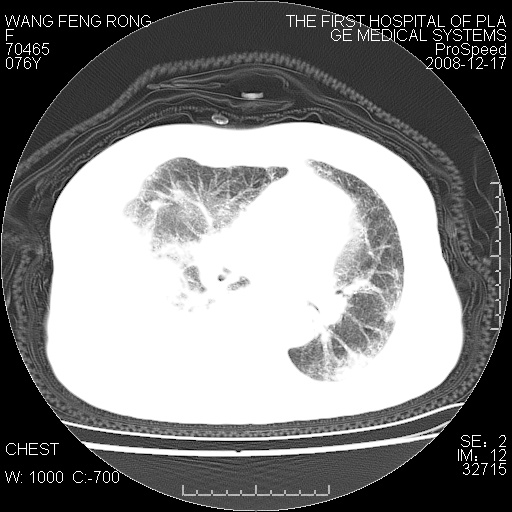

右侧胸腔积液,致右肺膨胀不全,双肺间质纤维化改变

1)考虑两肺炎症感染;不排除肺泡癌可能。2)两肺间质纤维化。3)右侧胸腔积液。

右侧胸腔积液,右肺膨胀不全伴感染(不除外肺癌),双肺间质水肿

结核(干酪性肺炎、支气管内膜结核、结核性胸水、淋巴结肿大钙化)

右肺大部实变,其内可见支气管影,但分支减少,宽窄不均,走行僵直,同侧胸腔大量积液;纵隔内见多发淋巴结影,但淋巴结大部有钙化;主动脉壁钙化;临床上病人咳嗽、消瘦。所以我考虑:1、结核(依据:右下肺实变,纵隔内淋巴结符合结核表现,同侧并发胸膜炎表现);2、支气管肺泡癌(依据:实变的肺组织内支气管分支减少,宽窄不均,走行僵直,没有把它放在第一诊断是因为没有看到明显肿大的淋巴结);3、动脉硬化(主动脉壁钙化就支持这个诊断)。

病理结果,肺泡癌